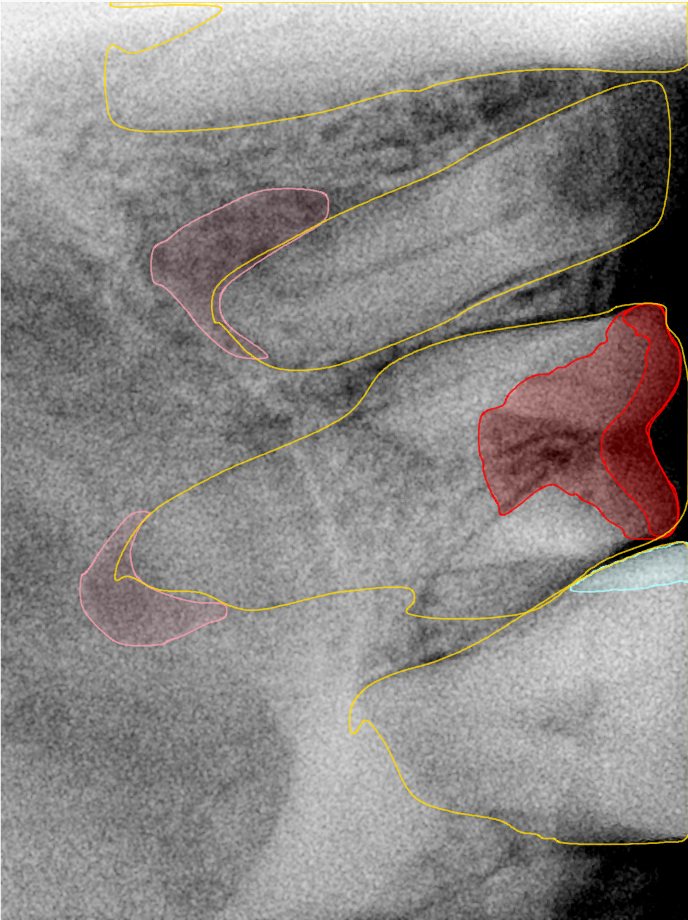

CR/DR 牙齿分割阶段记录

当前进展

- 完成了 CR/DR 牙齿相关分割训练

- 当前结果已经达到阶段预期,但仍有细节问题需要继续处理

相关测试

遇到的问题

- 训练过程中出现过 mask 下移问题

- 部分结果会出现 box 填充异常

- mask 边缘仍然有比较明显的锯齿感

第二版算法问题测试